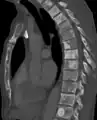

| Sclerosis of the bones of the pelvis due to prostate cancer metastases | |

Osteosclerosis is a disorder that is characterized by abnormal hardening of bone and an elevation in bone density. It may predominantly affect the medullary portion and/or cortex of bone. Plain radiographs are a valuable tool for detecting and classifying osteosclerotic disorders.[1][2] It can manifest in localized or generalized osteosclerosis. Localized osteosclerosis can be caused by Legg–Calvé–Perthes disease, sickle-cell disease and osteoarthritis among others. Osteosclerosis can be classified in accordance with the causative factor into acquired and hereditary.[2][1]